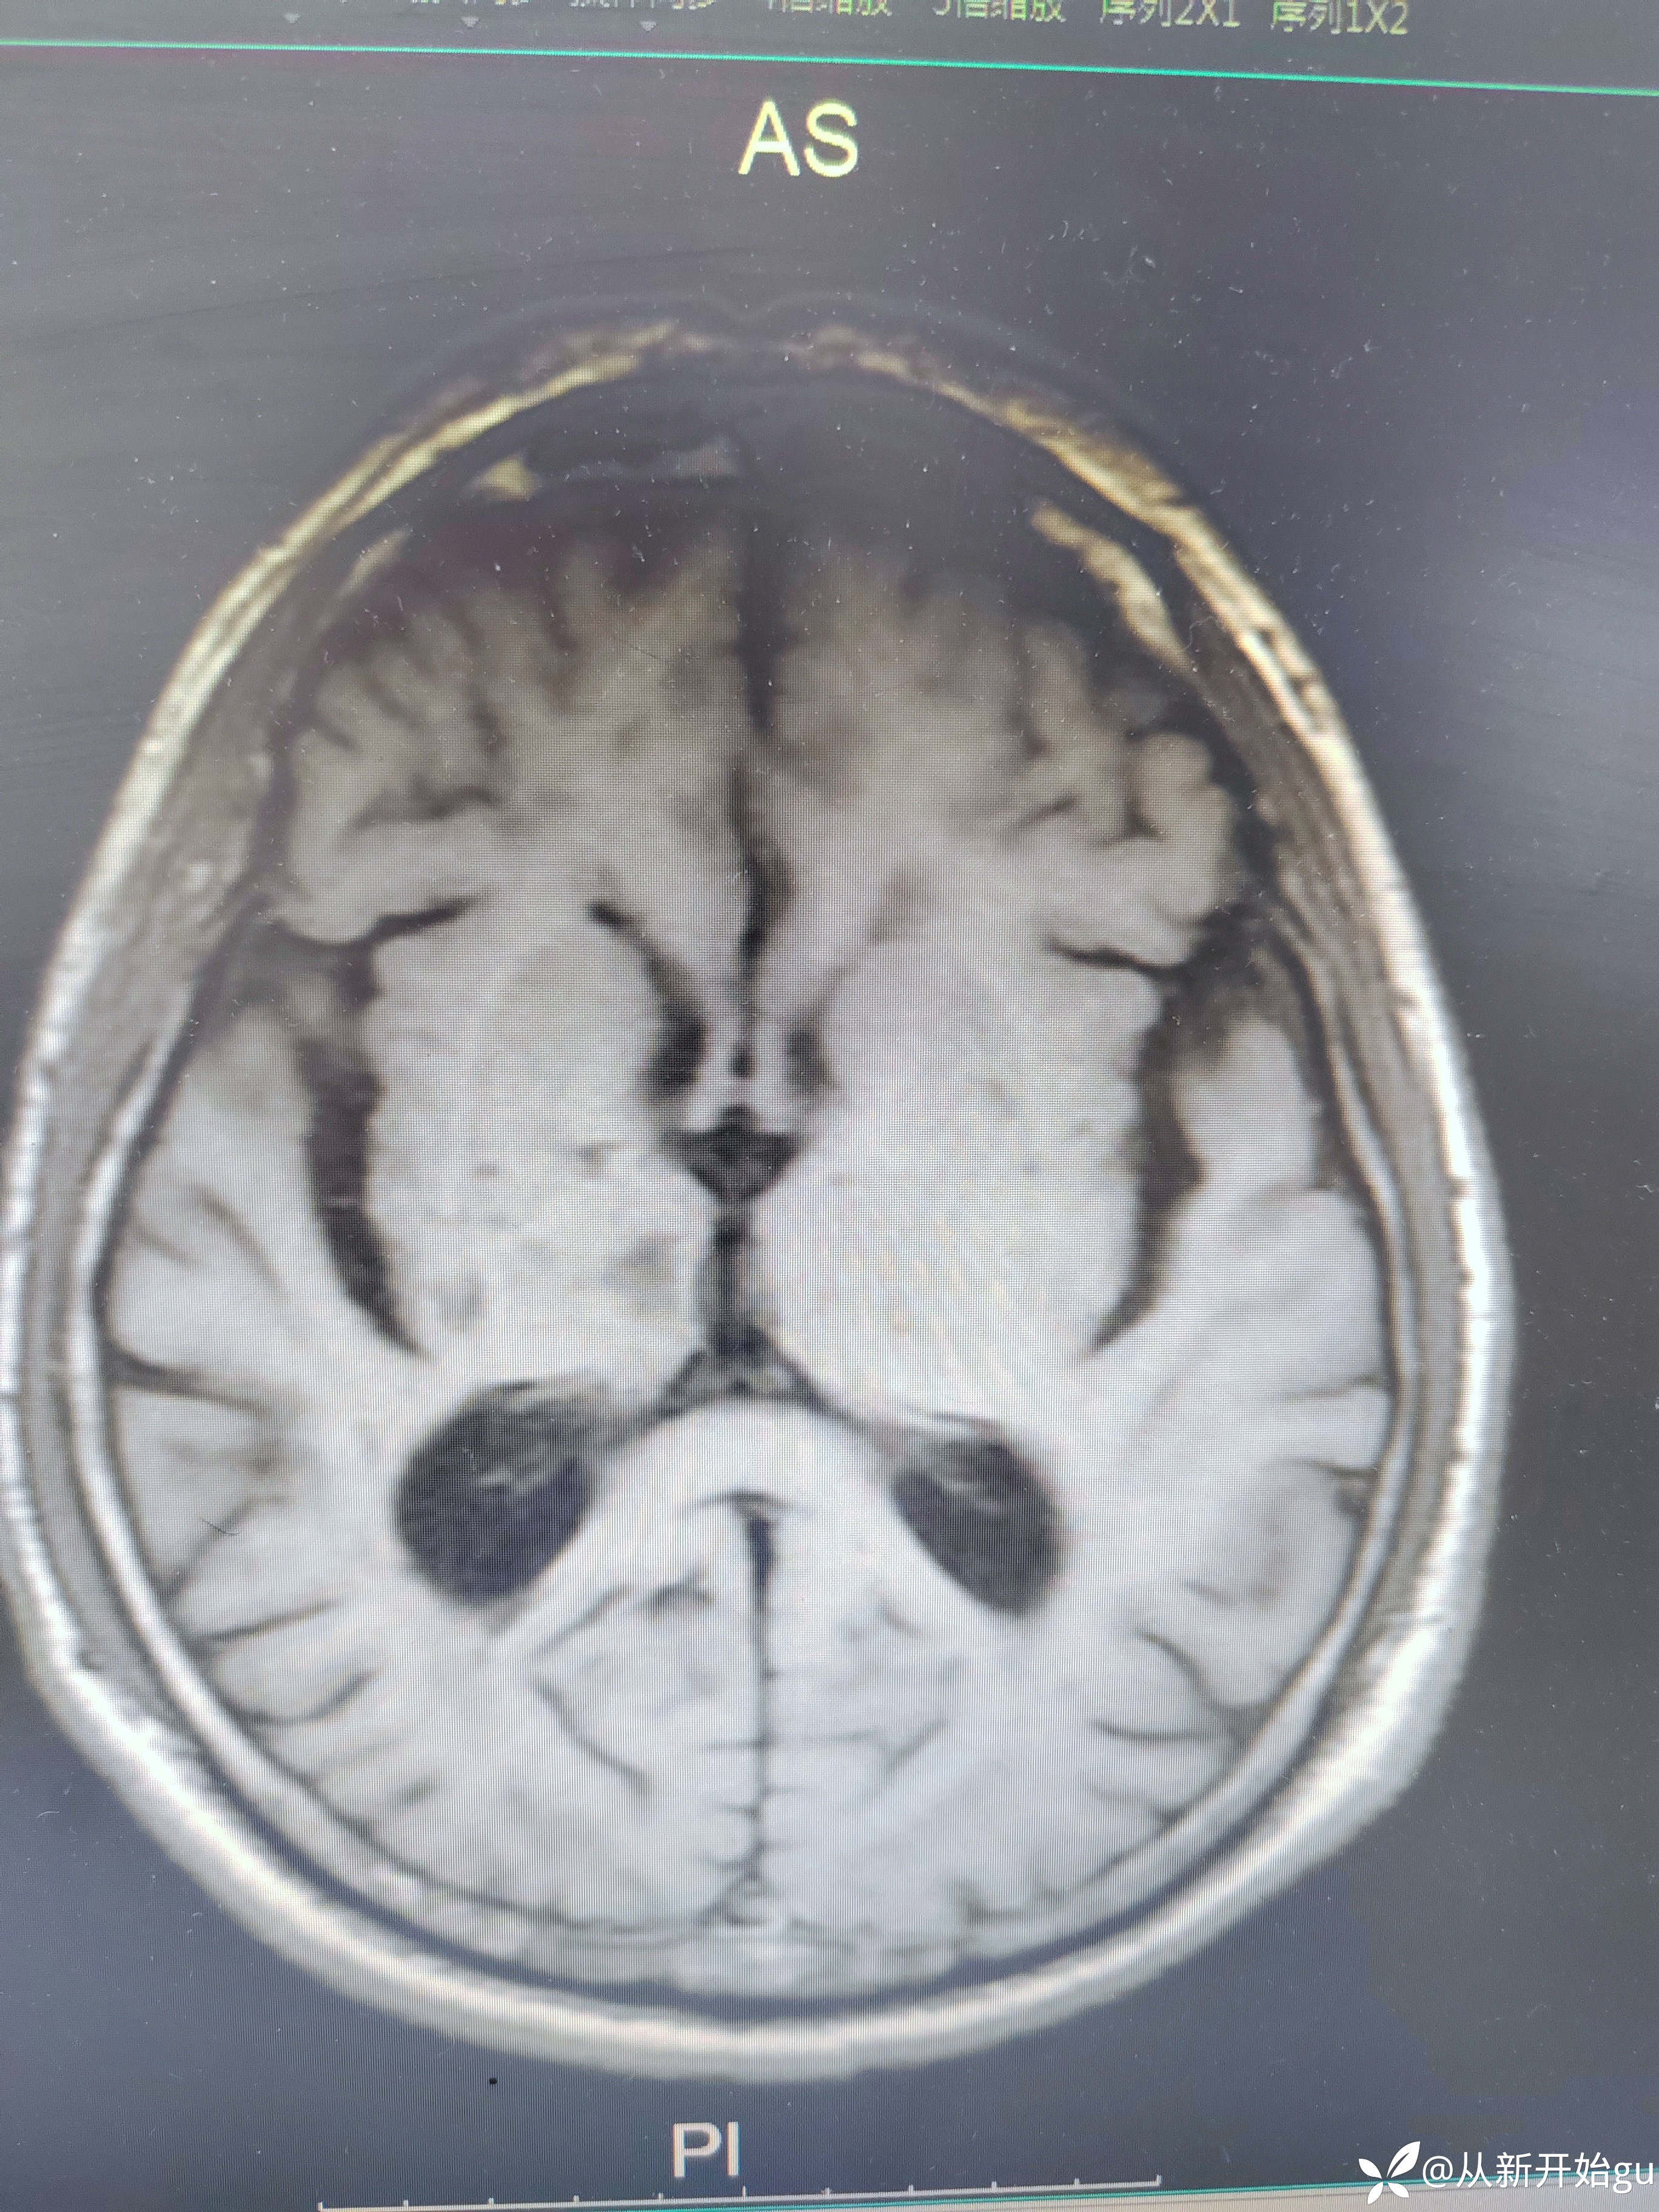

患者男性53岁,主因被发现左下肢活动障碍2.5小时来院,(患者下夜班,于上午9点休息,下午3点醒后出现症状)。既往脑梗死病史9个月,遗留言语不利及口角歪斜的症状。查体:右侧鼻唇沟稍浅,神舌右偏,左侧下肢肌力4级,左侧指鼻试验欠稳准,左侧巴氏征阳性。外院完善颅脑CT无出血改变。来院后完善核磁检查如图所示。